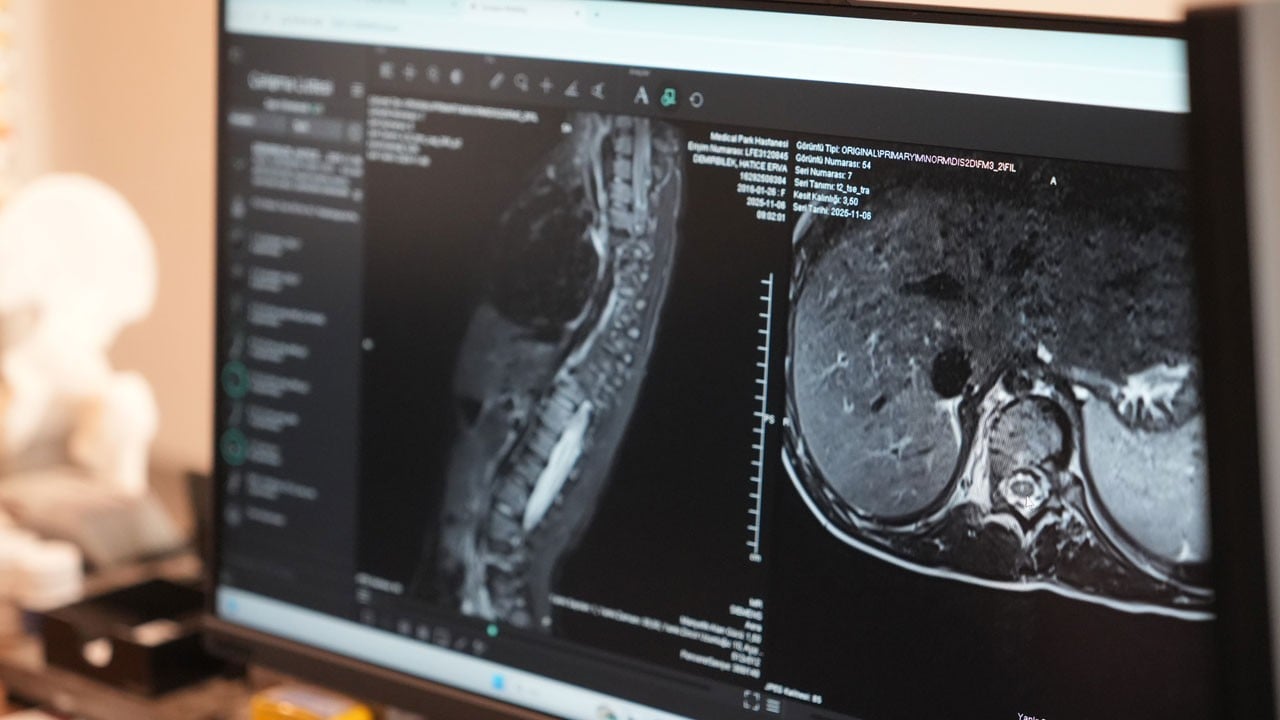

Erdem, tanı sürecine ilişkin de bilgiler vererek, "Skolyozun kesin tanısı ayakta çekilen bir röntgen filmiyle konur. Ancak öncesinde basit, hızlı ve etkili bir tarama yöntemi olan öne eğilme testini kullanıyoruz. Çocuk öne eğildiğinde kaburgalar veya bel bölgesindeki asimetri çok daha net şekilde görülür" şeklinde konuştu.